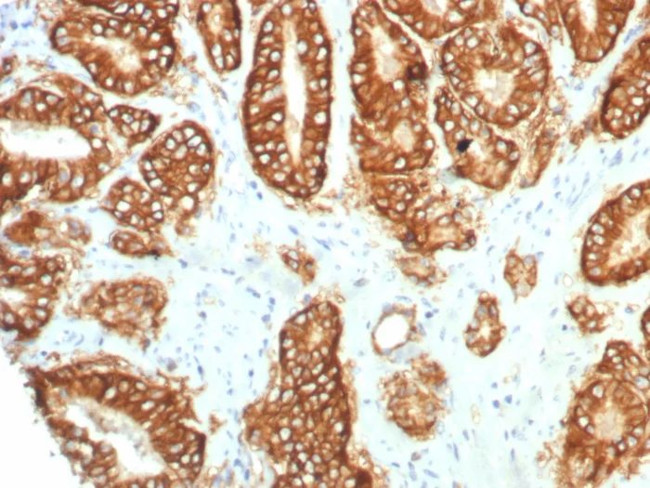

TACSTD2/TROP2 (Epithelial Marker) Antibody in Immunohistochemistry (Paraffin) (IHC (P))

TACSTD2/TROP2 (Epithelial Marker) Antibody (4070-RBM9-P1ABX) in IHC (P)

Formalin-fixed, paraffin-embedded human prostate carcinoma stained with TACSTD2 Recombinant Rabbit Monoclonal Antibody (TACSTD2/7349R). HIER: Tris/EDTA, pH9.0, 45 min. 2°C: HRP-polymer, 30 min. DAB, 5 min. {{ $ctrl.currentElement.advancedVerification.fullName }} 验证信息 View more